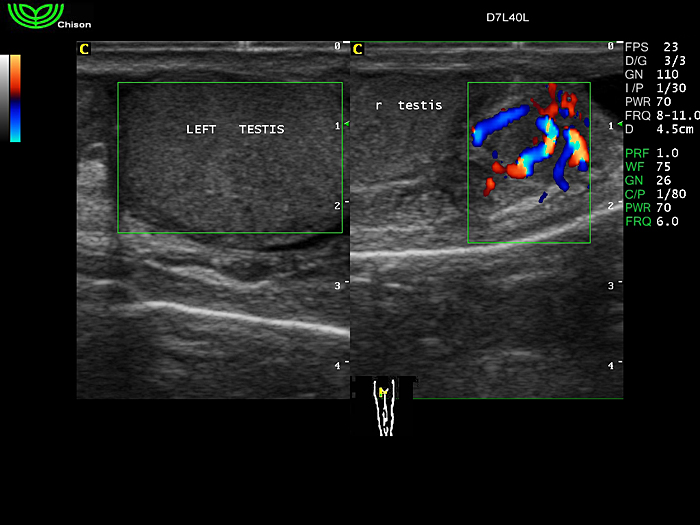

D7L40L 7.5МГц, линейный.

4.0МГц – 13.0 МГц. Применения: грудь, малые органы, нервы, сосуды, венозная катетеризация, мышцы и скелет, управление биопсией. |